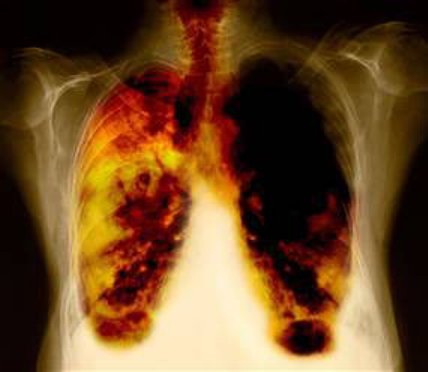

![]()  |

| Ung thư phổi |